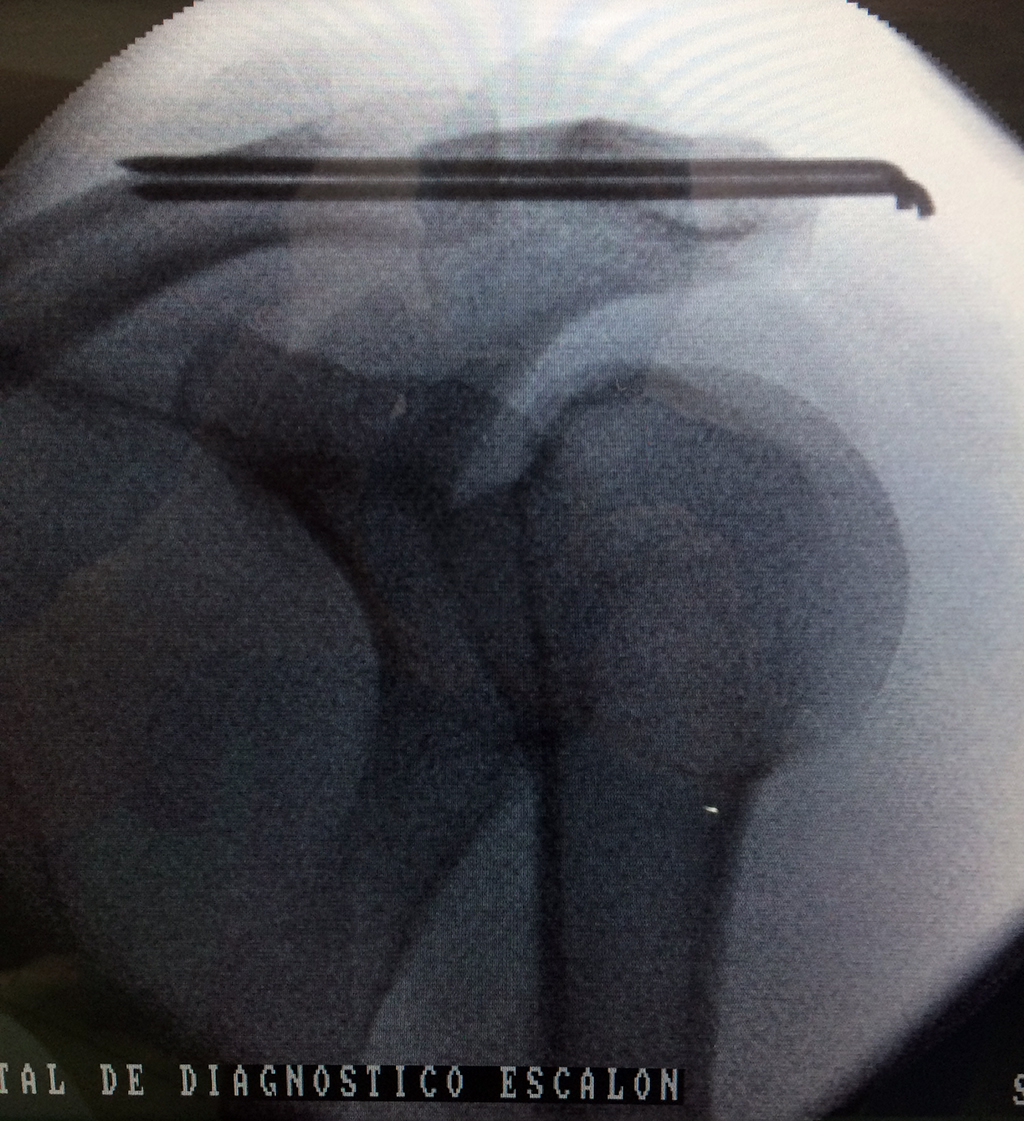

Cirugías de Codos - Clavícula